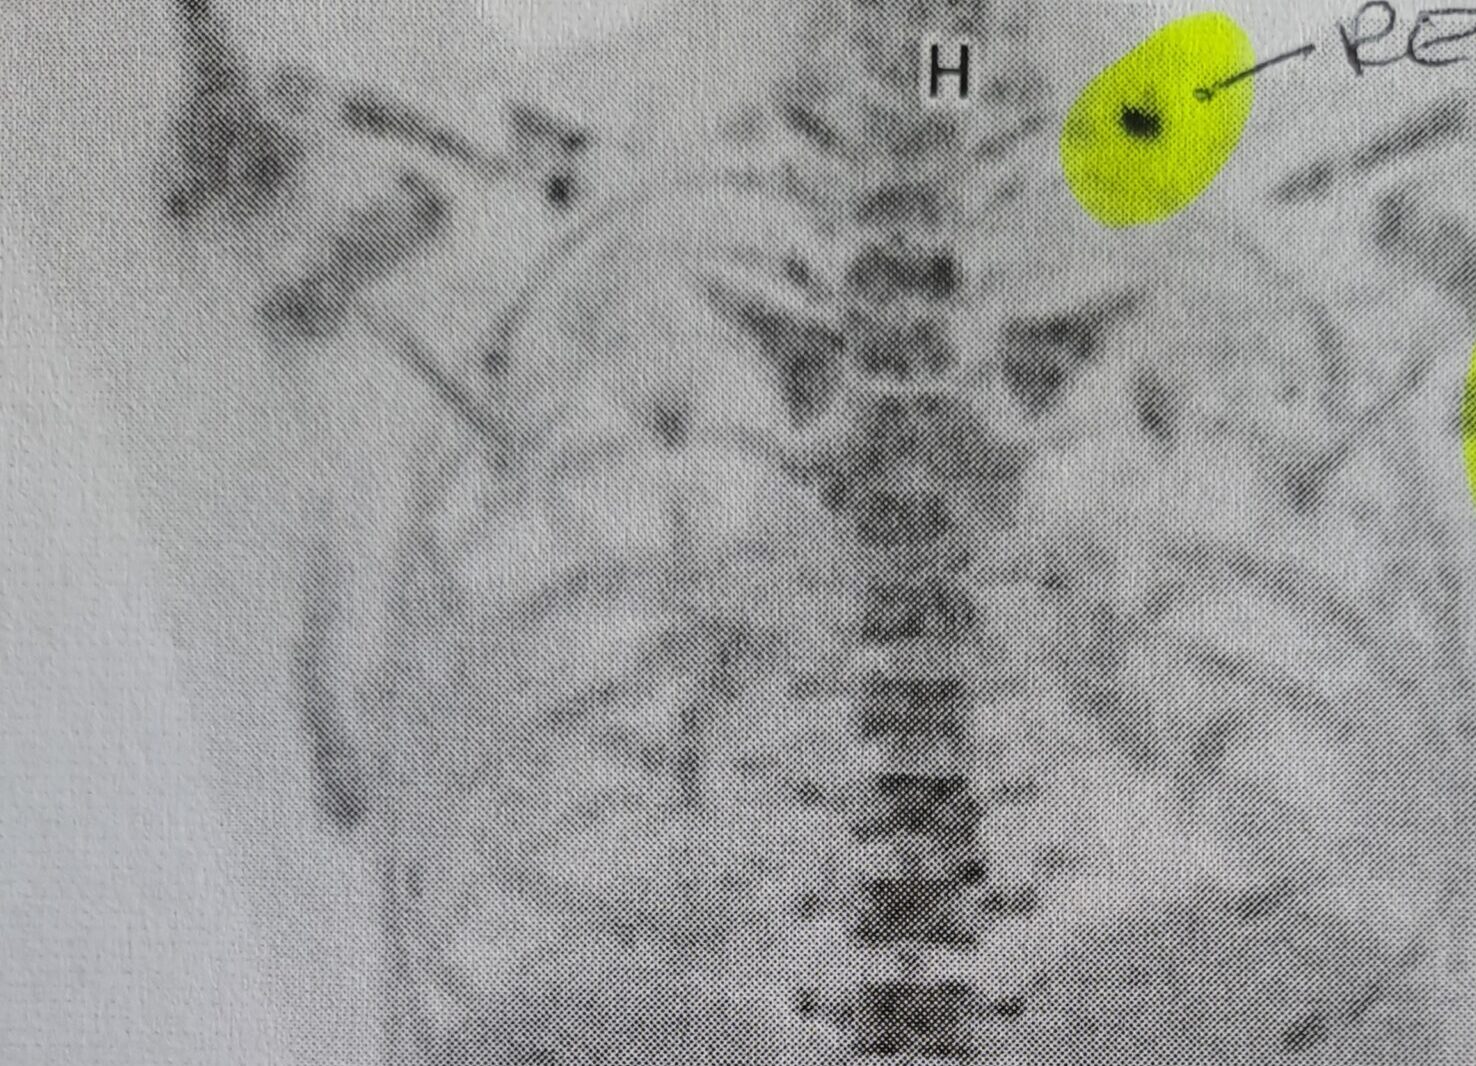

Leider muss ich einen Rückschlag hinnehmen – am PET-CT sind leider noch immer ein paar Hodgkin-Zellen zu sehen. Meine Onkologin besorgt mir freundlicherweise einen Screenshot von den beiden PET-CTs und da ist deutlich zu sehen, dass die Zellen zwar sehr stark zurückgegangen sind (JUHU!!) und nur mehr wenige auf der rechten Halsseite da sind. Aber dennoch bedeutet dies, dass 6 Zyklen gemacht werden müssen. Gerade die Tage, wo ich so müde und kraftlos bin, ist es psychisch schwer für mich. Alle sorgen rund herum, dass der Haushalt funktioniert und dass die Kinder betreut sind – aber ich fühle mich allein und bräuchte auch jemanden, der mich umsorgt, meine Hand hält oder mal einen Wickel für meinen Hals macht. Ich weine mich bei meinem Mann aus und weiß gleichzeitig, dass er alles mögliche macht, damit ich freigespielt bin und dass er auch oft überfordert ist.